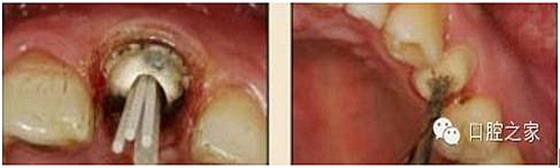

8.根管內(nèi)酸蝕劑的去除

使用全酸蝕粘結(jié)系統(tǒng)粘接纖維樁時,需要應(yīng)用磷酸凝膠對根管進行酸蝕處理,然后再徹底沖洗干凈。根管內(nèi)酸蝕劑的殘留是臨床上經(jīng)常發(fā)生且容易被忽視的問題,也是影響纖維樁粘接的重要因素之一。單獨使用三用槍即使反復(fù)沖洗也很難將根管內(nèi)的酸蝕劑清除干凈,尤其是后牙根管。臨床建議應(yīng)用注射器、三用槍和柱狀毛刷,三者聯(lián)合使用反復(fù)沖洗,以免酸蝕劑殘留于根管內(nèi)(圖 19-1至圖 19-4)。有條件者也可使用超聲波蕩洗根管。

圖19-1:冠部及根管全酸蝕。圖19-2:三用槍沖洗。圖19-3:注射器沖洗。 圖19-4:根管毛刷清洗。